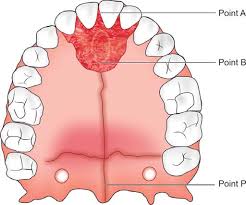

Blue grass

A felső első őrlőfogakon gyűrűvel rögzülő, a szájpadot vékony acélívvel áthidaló rögzített fogszabályzó készülék, mely közepén (a szájpadon) apró golyó található. Ezt a golyót nyelvvel pörgetni lehet, ezért gyerekeknél gyakran használjuk használjuk nyelvlökéses nyelés korrekciójára. A készülékkel játékosan érhető el a nyelv helyes pozícióba szoktatása.

A kép forrása: https://kieferorthopaedie.com/